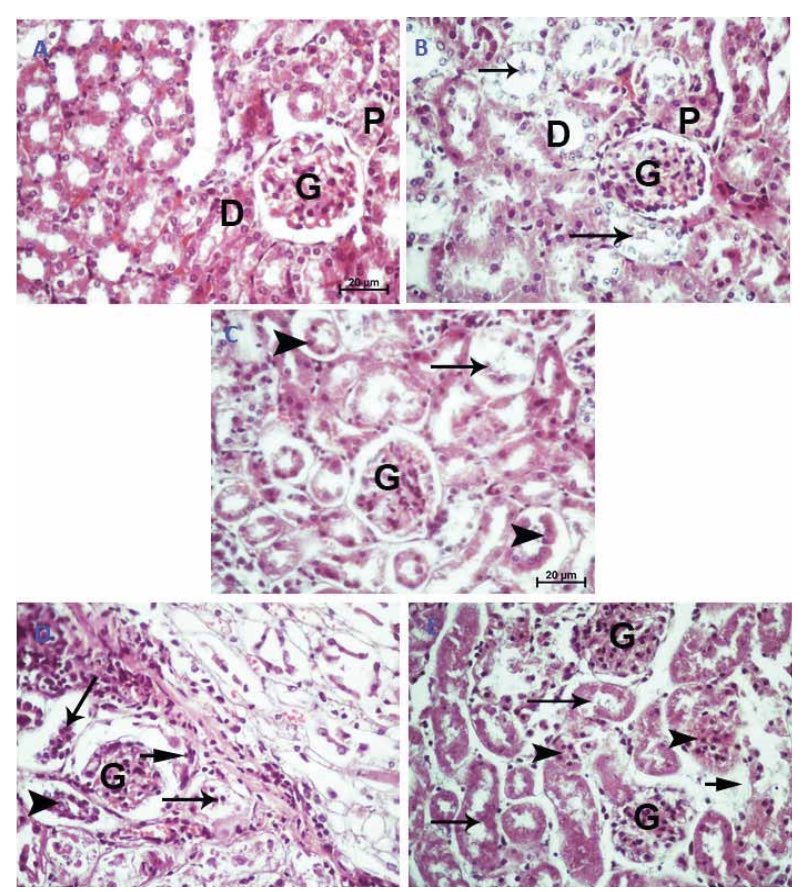

العينات النسيجية تم تحضيرها ببلوكات البرافين وتم تقطيعها وصبغها بصبغة H&E وعينات DNA حفظناها في (-20) ˚ عشان نحافظ عليها من التكسر. وبعدها تمت معالجتها وقراءتها على gel electrophoresis

بالنسبة للكبد نتائجها كانت جيدة سواء في درجة حرارة الغرفة او درجة منخفضة، طبعًا مع تأخير واضح للتغيرات النسيجية في درجة حرارة 4˚ والتغيرات كانت عبارة عن فجوات بين الخلايا، انكماش او تكسر في النواة وبعدها صارت العينات غير مميزة ودخلت في العشوائية

بالجانب الآخر الكلى كانت صورها نوعًا ما سيئة والتحلل فيها كان بصورة كبيرة في كل درجتي الحرارة بسبب وجود الأنزيمات بشكل أكبر في الكلى وأيضًا السموم من الجسم.😵‍💫

ولكن أيضًا التحلل كان بصورة أقل في درجة الحرارة المنخفضة..